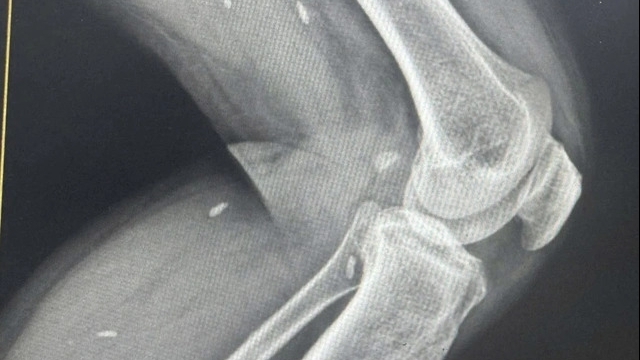

Bệnh nhân nhập viện trong tình trạng sốc mất máu, ý thức hoảng loạn, bàn tay phải đứt xương khối xương cổ tay phải, đứt mạch máu trụ quay, đứt thần kinh giữa, đứt thần kinh trụ, đứt gân gấp ngón 2,3,4,5 bàn tay phải và có bệnh nền đái tháo đường type 2 kèm theo.

Tại phòng mổ, các bác sỹ đã tiến hành rửa, cắt lọc sạch vết thương, nối cung động mạch gan tay nông và nối cung động mạch gan tay sâu, nối thần kinh giữa và thần kinh trụ vi phẫu, nối gân gấp nông và gân gấp sâu ngón 2 3 4 5 bằng kính vi phẫu, nắn chỉnh ổ gãy khối xương cổ tay phải về vị trí giải phẫu, kết hợp xương khối xương cổ tay phải.